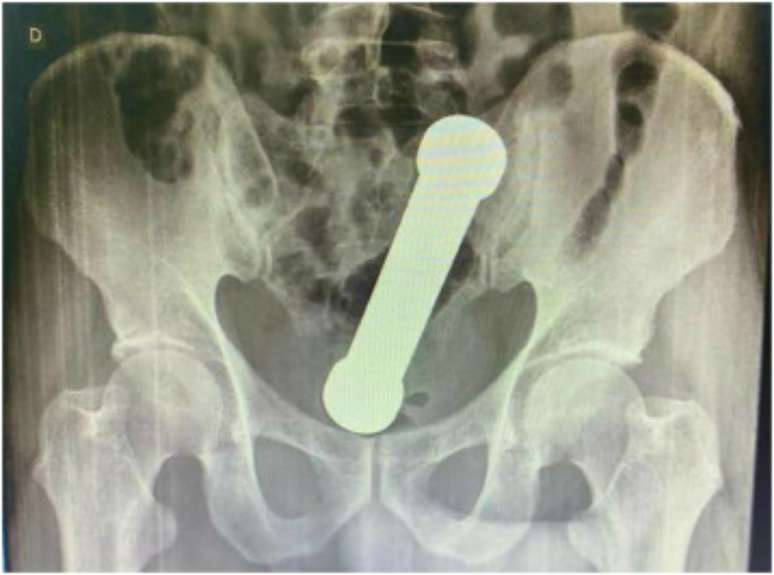

O caso de um paciente em Manaus (AM) virou artigo científico em uma revista internacional de medicina por se tratar de uma ocorrência bem inusitada. Um homem de 54 anos procurou atendimento médico na capital amazonense com dores no abdômen e dificuldade de evacuar.

Os médicos solicitaram exames para descobrir a origem do problema e se surpreenderam com as imagens de radiografia, que revelaram um halter, aquele peso de mão usado em academias, dentro do corpo do paciente.

O objeto tinha 20 centímetros e dois quilos. Foi necessário um procedimento cirúrgico para anestesiar o homem e poder retirar o halter de seu corpo. A cirurgia foi bem sucedida e o paciente recebeu alta após três dias internado.

O episódio foi descrito na International Journal of Surgery Case Reports com o título ”manejo de incomum corpo estranho retal” e com algumas fotos para ilustrar a excepcionalidade do caso.